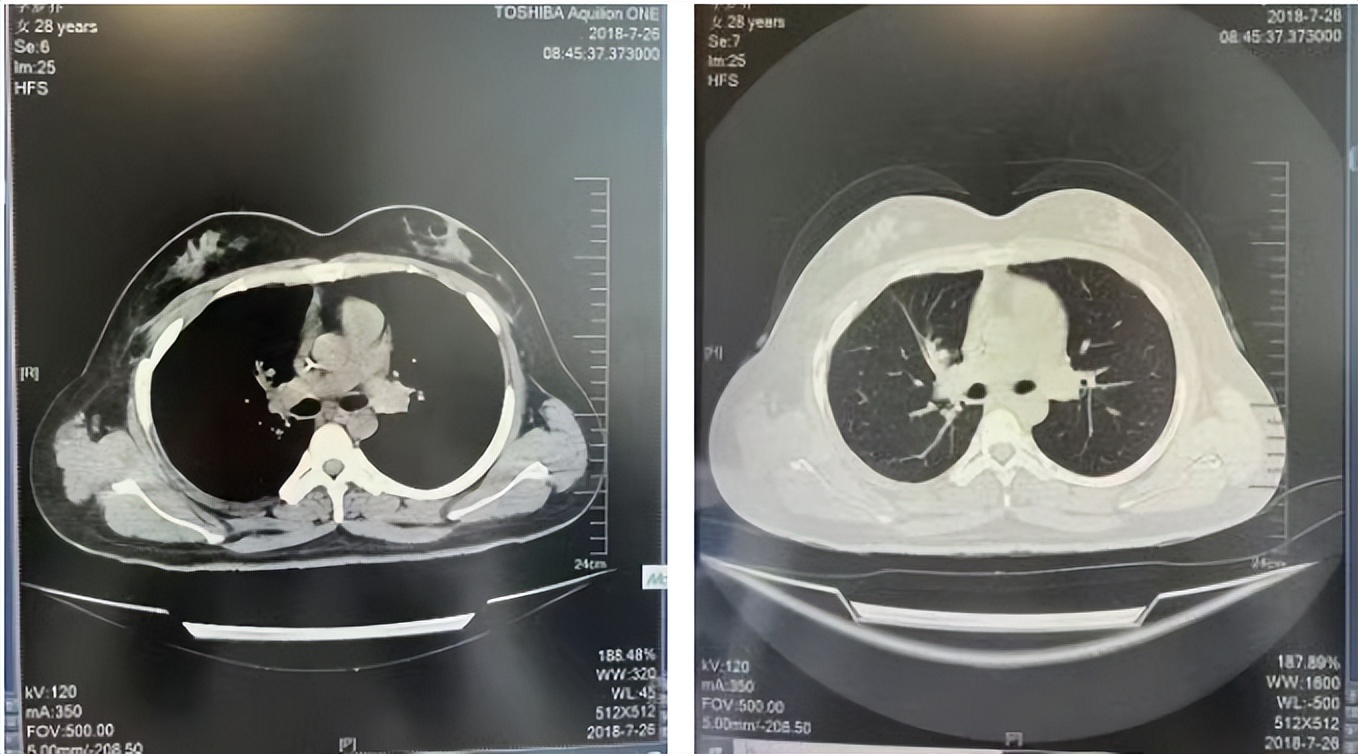

2016年1月复查CT提示支气管截断可见新发小结节,一线治疗采用培美曲塞+DDP方案化疗4周期(培美曲塞3.36,DDP 480mg)。化疗后复查胸部CT:右肺见不规则结节样影,最大层面大小约19mm*8mm,较前比较明显增大,疗效评估PD。2017.3-2017.4予单药多西他赛化疗3周期,疗效评估SD。2018年5月末复查CT提示结节较前增大,评效为PD,2018年6-10月予多西他赛+CBP化疗4周期,疗效评估SD。2022年5月患者出现活动后气短,复查胸部CT示右肺膨胀不良;右侧胸腔积液增多。胸腔积液包埋病理示符合肺腺癌细胞。行NGS基因检测:EML4:exon13-ALK:exon20融合。PD-L1(克隆号22C3)TPS<1%。

临床诊断:右肺上叶恶性肿瘤rT0N0M1a IVA期(第9版分期);恶性胸腔积液。

诊疗经过:2022年5月始口服克唑替尼3个月,出现肝功能异常(DILI 2级伴临床症状),改用恩沙替尼靶向治疗至今,目前评效为维持PR。恩沙替尼应用期间出现轻度肝功能异常(DILI 1级),对症处理后好转。截止目前PFS 33个月。

2018.07

2022.05

2022.08

2023.05

2024.12